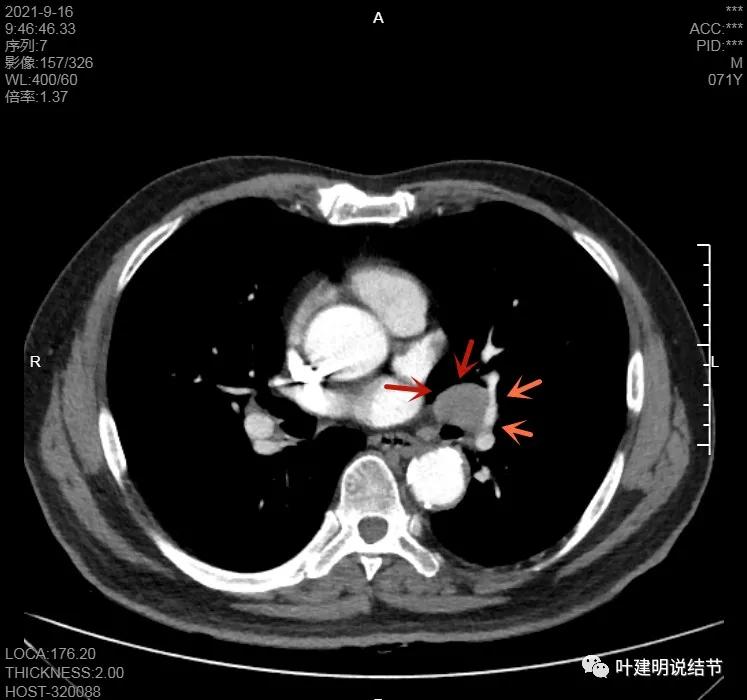

淋巴结巨大,部分包绕肺血管,但仍未见明显侵犯血管壁

肺血管受压明显,气管内壁感觉也是光滑的

以上诸图均示肿大淋巴结挤压肺血管,但未见确切侵犯破坏,支气管内壁也感觉是光滑的,没有肿瘤突向管腔